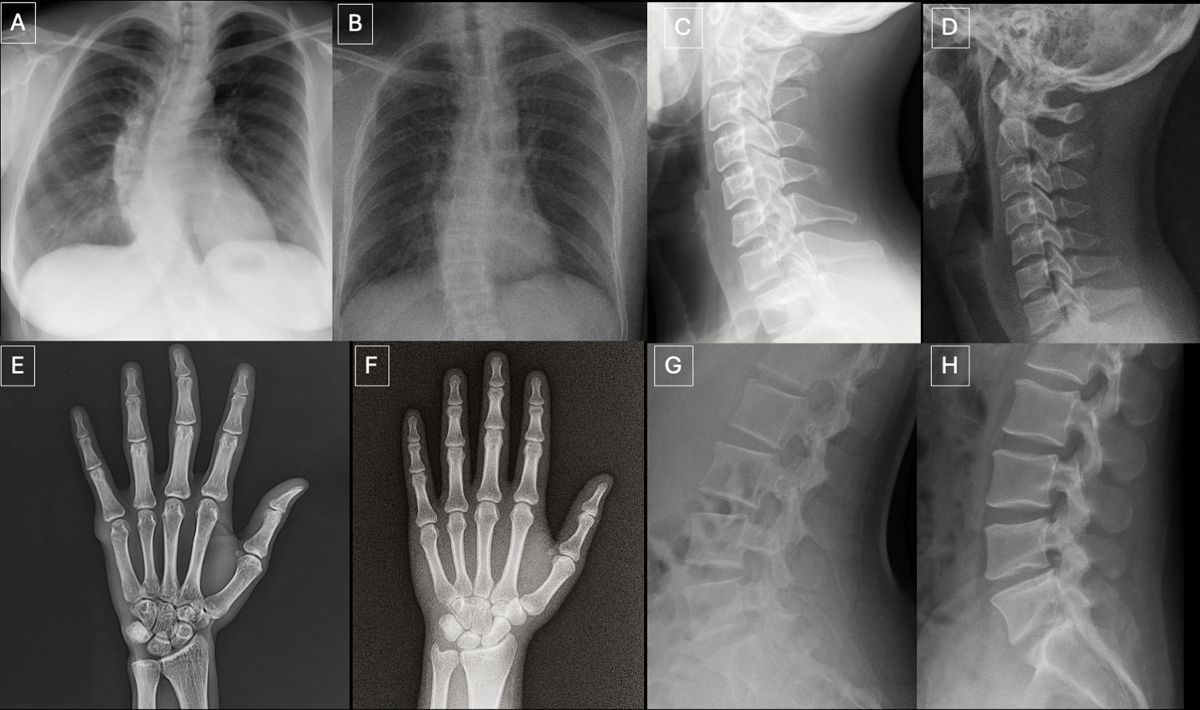

この問題は、北米放射線学会(RSNA)の査読付き学術誌『Radiology(ラジオロジー)』に掲載された最新の研究結果で明らかになった。研究では、6カ国・12施設の放射線科医17人に胸部X線(レントゲン)画像を見せて評価してもらった。用意した画像154枚のうち、半数は本物のレントゲン写真で、残りはAI生成されたものだった。

AI画像が混在していることを知らせない状態では、見せられた画像を「疑わしい」と判断した医師は41%にとどまった。一方、偽造された画像を探すよう指示されると、読影の精度は75%に上昇し、最も精度の高い読影をした医師の正答率は92%を記録した。一方、最も精度の低かった読影医の正答率は58%だった。放射線科医としての経験の長さは、測定可能な差をもたらさなかった。

この研究では胸部X線画像を使用したが、研究結果から示唆される問題の影響は医療記録全般に及ぶ。